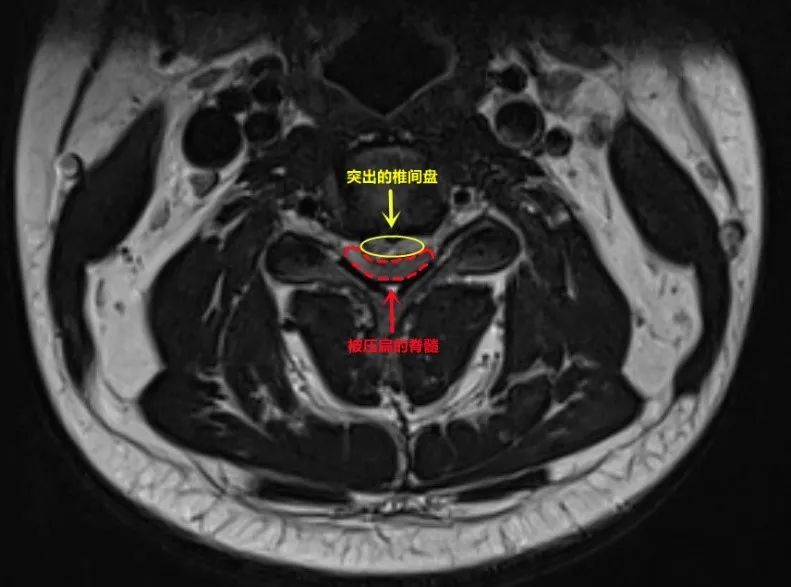

對(duì)于勞累的上班族來說 久坐不動(dòng),經(jīng)常覺得肩酸背痛 這種時(shí)候 不少會(huì)選擇去按摩 神清氣爽、活力滿滿 身心舒暢…… 當(dāng)問起每一個(gè)去過按摩店的人感受時(shí) 他們會(huì)說出一大堆類似的詞 定期做按摩 甚至已經(jīng)成為不少人的習(xí)慣 但是 按摩不是你想按就能按 深圳一男子就按出大事來了 深圳小伙“落枕”按摩 右邊身體突然癱了 小何(化名)是深圳某公司的職員,從事外貿(mào)出口工作,常年要在電腦前工作,頸部、背部等局部肌肉長期緊張、勞損。偶爾勞累后,肩膀脖子都會(huì)酸脹。 前一陣子,他的脖子突然“落枕”了,白天歪著脖,晚上睡不好,“落枕”后,在朋友的推薦下,小何找到一家按摩理療店,專門選了一套針對(duì)頸部的按摩套餐。 小何回憶,那位老師傅的手勁有點(diǎn)猛,咔咔一頓操作下來,疼歸疼,但事后確實(shí)感覺輕松了一些。隔了幾天,小何又去按了一次。 專業(yè)按摩來一套 三天后的早晨,小何只是彎腰放東西的一個(gè)動(dòng)作,突然感覺右邊身體從脖子到腰這條“筋”像是抻了一下,當(dāng)時(shí)沒太在意,繼續(xù)上班去了。 工作忙碌中,小何漸漸感覺右半邊身子有點(diǎn)兒“鈍”,胳膊也軟綿綿的,沒力氣,再轉(zhuǎn)頭去看點(diǎn)著鼠標(biāo)的手指,好像已經(jīng)不太受控制了。 小何一下子慌神了,勉強(qiáng)用左手打字給家人、同事發(fā)信息,前后也就10分鐘,他的右手已經(jīng)完全不能動(dòng)了,同事們趕緊帶著他去醫(yī)院。 等趕到深圳大學(xué)總醫(yī)院,小何的整個(gè)右邊身子已經(jīng)“癱”了,右腿站不住、走不了,坐在輪椅上被同事推到了急診科門口。 術(shù)前右胳膊無法自主抬起 罪魁禍?zhǔn)渍业搅?/span> 小伙緊急手術(shù) 身體癱了,好在意識(shí)還很清醒,小何努力回憶著這一早上的每個(gè)環(huán)節(jié)。 醫(yī)生初步判斷,他這是“中風(fēng)”了。醫(yī)院立即啟動(dòng)綠色通道急查頭顱CT,幸運(yùn)的是,暫時(shí)沒發(fā)現(xiàn)他的腦內(nèi)有出血性病變。醫(yī)院迅速以“急性腦梗死”把他收入神經(jīng)內(nèi)科病房。 最后,經(jīng)過一系列檢查 導(dǎo)致他偏癱的罪魁禍?zhǔn)?/span> 終于找到了 是“頸椎間盤突出癥(C3/4節(jié)段)”壓迫頸髓 導(dǎo)致了右側(cè)肢體偏癱 頸椎間盤脫出,小何被轉(zhuǎn)到脊柱骨病科。經(jīng)脊柱骨病科全科討論,需要盡快手術(shù)。 緊急手術(shù)后 經(jīng)過醫(yī)生的悉心治療 如今小何已經(jīng)康復(fù) 可以正常返工上班了 醫(yī)生提醒: 這些人按摩要慎重 深圳大學(xué)總醫(yī)院脊柱骨病科張智慧主任醫(yī)師特別提醒—— 對(duì)于已經(jīng)患有椎間盤突出的人群,推拿按摩有加重椎間盤突出的風(fēng)險(xiǎn)。 張智慧主任醫(yī)師從事脊柱外科臨床工作30余年,見過椎間盤突出經(jīng)推拿按摩后癥狀加重的病例不在少數(shù),嚴(yán)重者可出現(xiàn)肢體癱瘓。但并不是每個(gè)患者都能像何先生一樣幸運(yùn),通過手術(shù)獲得了神經(jīng)功能的完全恢復(fù)。不少患者手術(shù)后脊髓神經(jīng)功能無法完全恢復(fù),或多或少殘留肢體麻痛或乏力,甚至大小便功能障礙,影響生活和工作。 因此,平時(shí)有頸肩痛、腰腿痛的人群,最好到醫(yī)院就診,排查有無椎間盤突出,若明確有椎間盤突出,那么推拿按摩等一定要慎重,建議應(yīng)遵循脊柱外科?漆t(yī)師診療方案,才能獲得更安全有效的治療。 對(duì)一些身體上的不適 比起打針吃藥 大家對(duì)按摩的接受度似乎更高 除了醫(yī)院康復(fù)科的理療和中醫(yī)的穴位按摩 各種美容院、養(yǎng)生館的按摩也很受青睞 在不少人心里 按摩的功效已經(jīng)從單純的緩解肌肉關(guān)節(jié)痛 延伸到了全身調(diào)理 哪里痛了去按一按 是不少人的第一反應(yīng) 但類似下面這樣的新聞的不斷出現(xiàn) 讓大家害怕又困惑 但其實(shí) 按摩本身就可能存在風(fēng)險(xiǎn)、 甚至易誘發(fā)或加重疾病 下面幾類人,按摩時(shí)就應(yīng)當(dāng)慎重 01 剛扭傷者

例如患有椎體結(jié)核、腫瘤等疾病,應(yīng)立即去?浦委。頸椎病、腰椎間盤突出等患者如果按摩不當(dāng),易加重癥狀。

懷疑自己有骨關(guān)節(jié)疾病者,應(yīng)在正規(guī)醫(yī)院骨科請(qǐng)醫(yī)生明確診斷,排除相關(guān)禁忌癥后,遵醫(yī)囑進(jìn)行按摩推拿。椎間盤突出等疾病的患者,常需要先拍片,完成相關(guān)檢查后,才能更好地觀察軟組織,確定能否按摩。